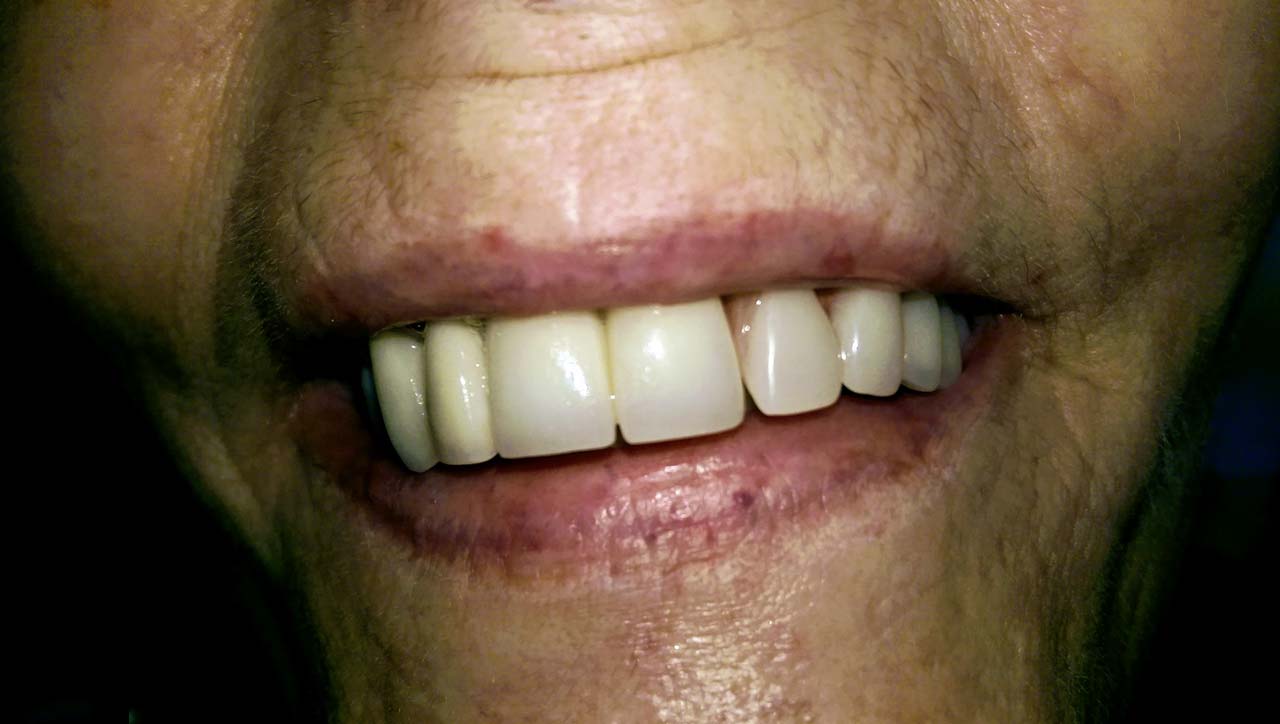

Teljes fogatlanság helyreállítása 2 nap alatt

Teljes fogatlanság helyreállítása 2 nap alatt azonnal terhelhető svájci IHDE implantátumokkal és PMMA műanyag hidakkal. Intraorális szkennerrel vettünk lenyomatot az implantáció után, és erre a digitális mintára készítette el a fogtechnika a hidak digitális tervezését, majd faragta ki műanyagból. Ezt a gyors munkát az azonnal terhelhető implantátumok és a digitális lenyomat, tervezés segítségével tudtuk megcsinálni mindössze 2 nap alatt. Dr. Kelemen Péter és a Symbion Fogtechnika munkája.